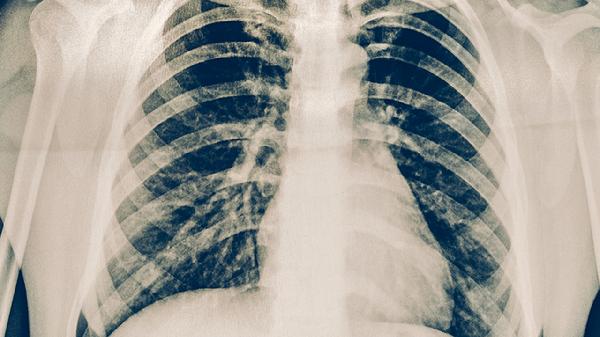

肺结核患者除规范用药外,需保证充足营养摄入,每日蛋白质供给应达到每公斤体重1.5-2克,优先选择鸡蛋、鱼肉等优质蛋白。适当补充维生素A、维生素D和锌有助于黏膜修复。治疗期间须严格遵医嘱完成全程用药,避免擅自停药导致治疗失败或耐药。定期进行痰菌检查及影像学复查,保持居住环境通风良好,咳嗽时注意掩住口鼻。出现食欲减退、皮肤黄染等异常症状应及时就医。